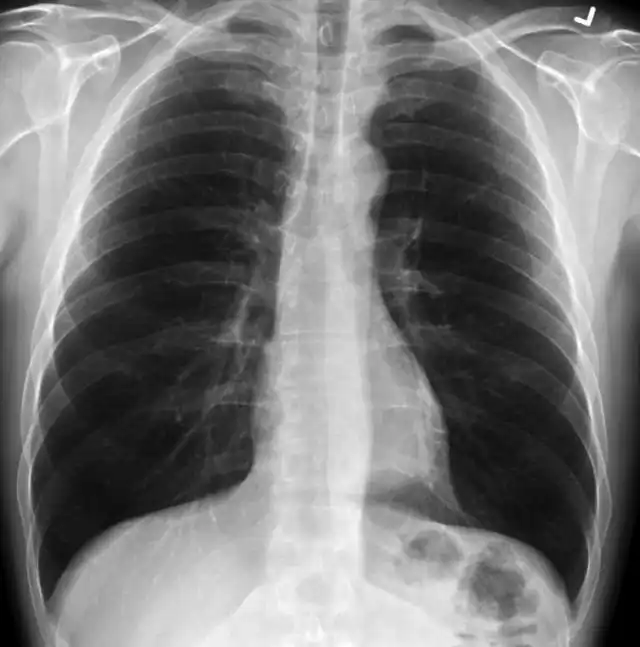

Так выглядят лёгкие здорового человека. Чёрные области - это воздух.